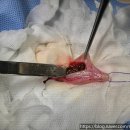

• 선부중앙동물의료센터 | 안산 고양이 이물 수술 전문 | 선부중앙동물의료센터 소화기 수술 후기 및 입원 관리

안녕하세요, 안산의 모든 반려가족분들! 선부중앙동물의료센터입니다. 🐾 고양이를 키우는 집사님들이라면 한 번쯤 '혹시 우리 아이가 이걸 먹은 건 아닐까?' 하는 걱정에 가슴이 철렁했던 적 있으실 거예요. 고양이는 호기심이 많고 혀의 돌기 때문에 이물질을 삼키기 쉬운 구조를 가지고 있거든요. 오늘은 소화기 이물...

안산 반려동물 건강의 중심, 선부중앙동물의료센터(2026-04-24 14:45:00)